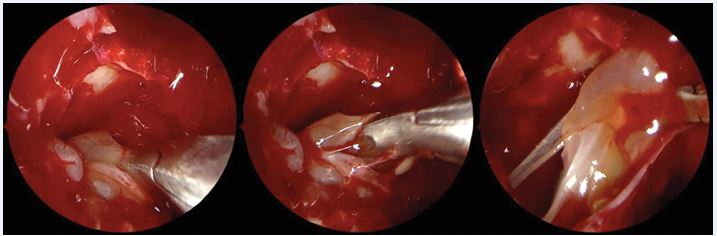

https://www.jscimedcentral.com/public/assets/images/uploads/image-1764067815-1.JPG

Figure 2 Reboot surgery approach. Image sequence showing the antrum grasping forceps (Heuwieser) removing polypoid mucosa from the entire right maxillary sinus.

https://www.jscimedcentral.com/public/assets/images/uploads/image-1764067885-1.JPG

Figure 3 Exposure of the periosteum of the right maxillary sinus after removal of the lining diseased mucosa.

Next, the diseased mucosa of the anterior and posterior ethmoids must be removed, including lamina papyracea, skull base, and lateral face (and anterior portion, when necessary) of the middle turbinate (Figure 4).

https://www.jscimedcentral.com/public/assets/images/uploads/image-1764067972-1.JPG

Figure 4 Removal of diseased mucosal tissue from the right ethmoid sinus using blunt, curved, atraumatic suction instruments.